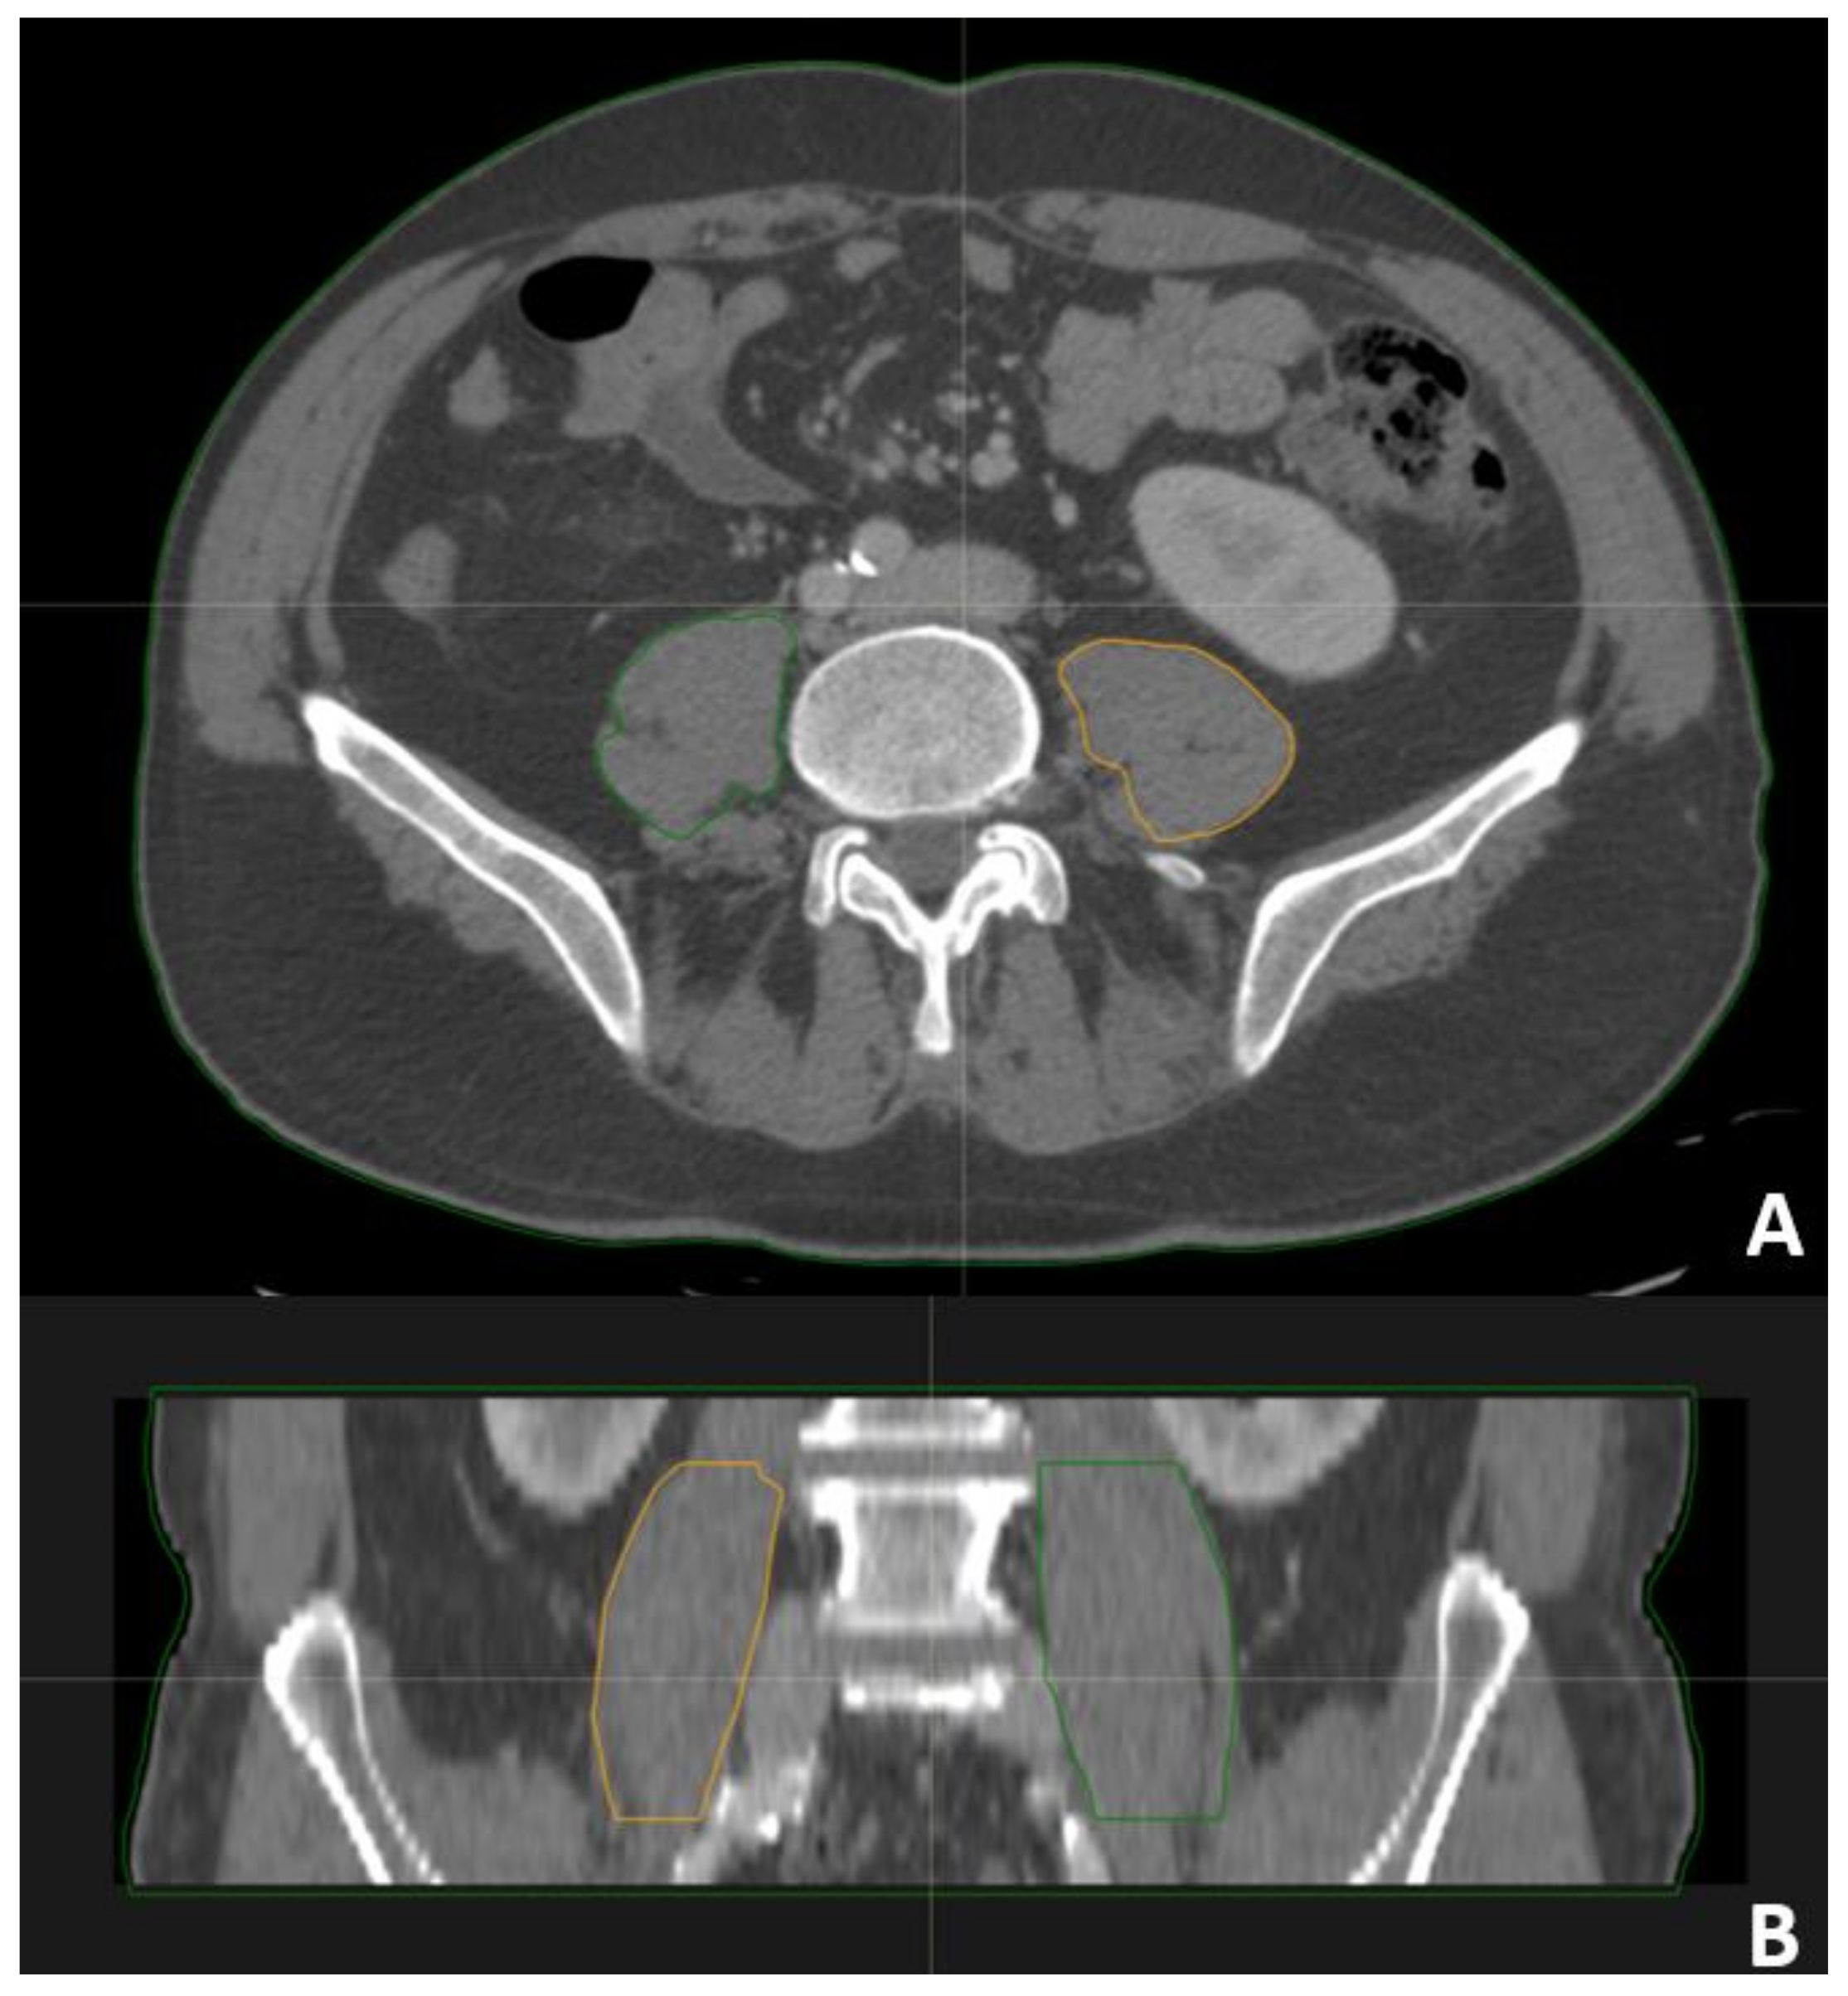

2.4. Psoas Contouring